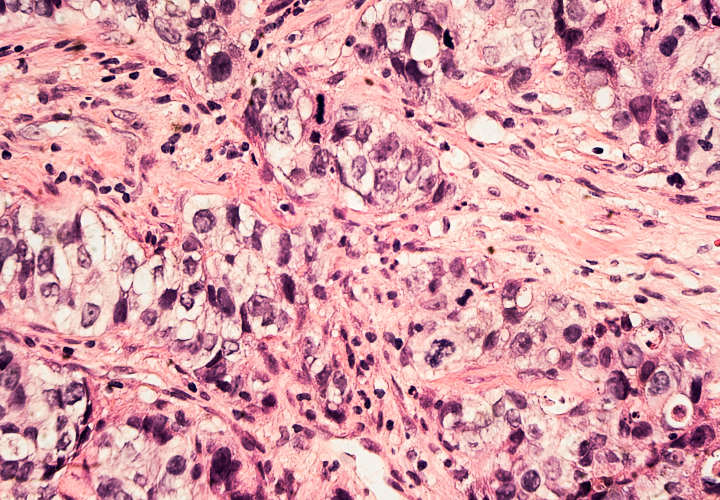

La importancia del mal diagnóstico en el cáncer de mama

El cáncer de mama es la primera causa de muerte en mujeres en todo el mundo, de acuerdo a la Sociedad Americana de Cáncer.